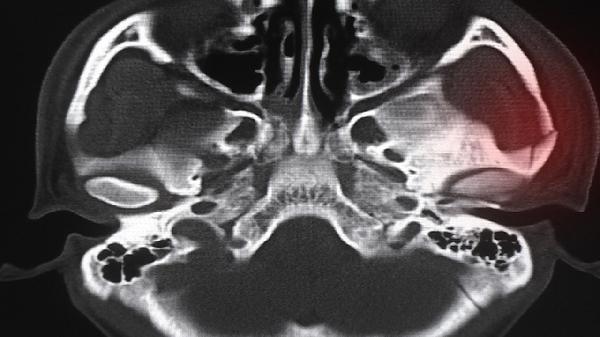

少数人群存在胸骨柄与胸骨体连接处结构异常,如胸骨角过突或关节面不平整,活动时易产生摩擦音。通常自幼即可发现,但多数无需特殊处理。若成年后突发弹响且伴随胸闷气短,需排除马凡综合征等结缔组织病,通过胸部CT三维重建明确骨骼形态,必要时进行胸骨成形术矫正。